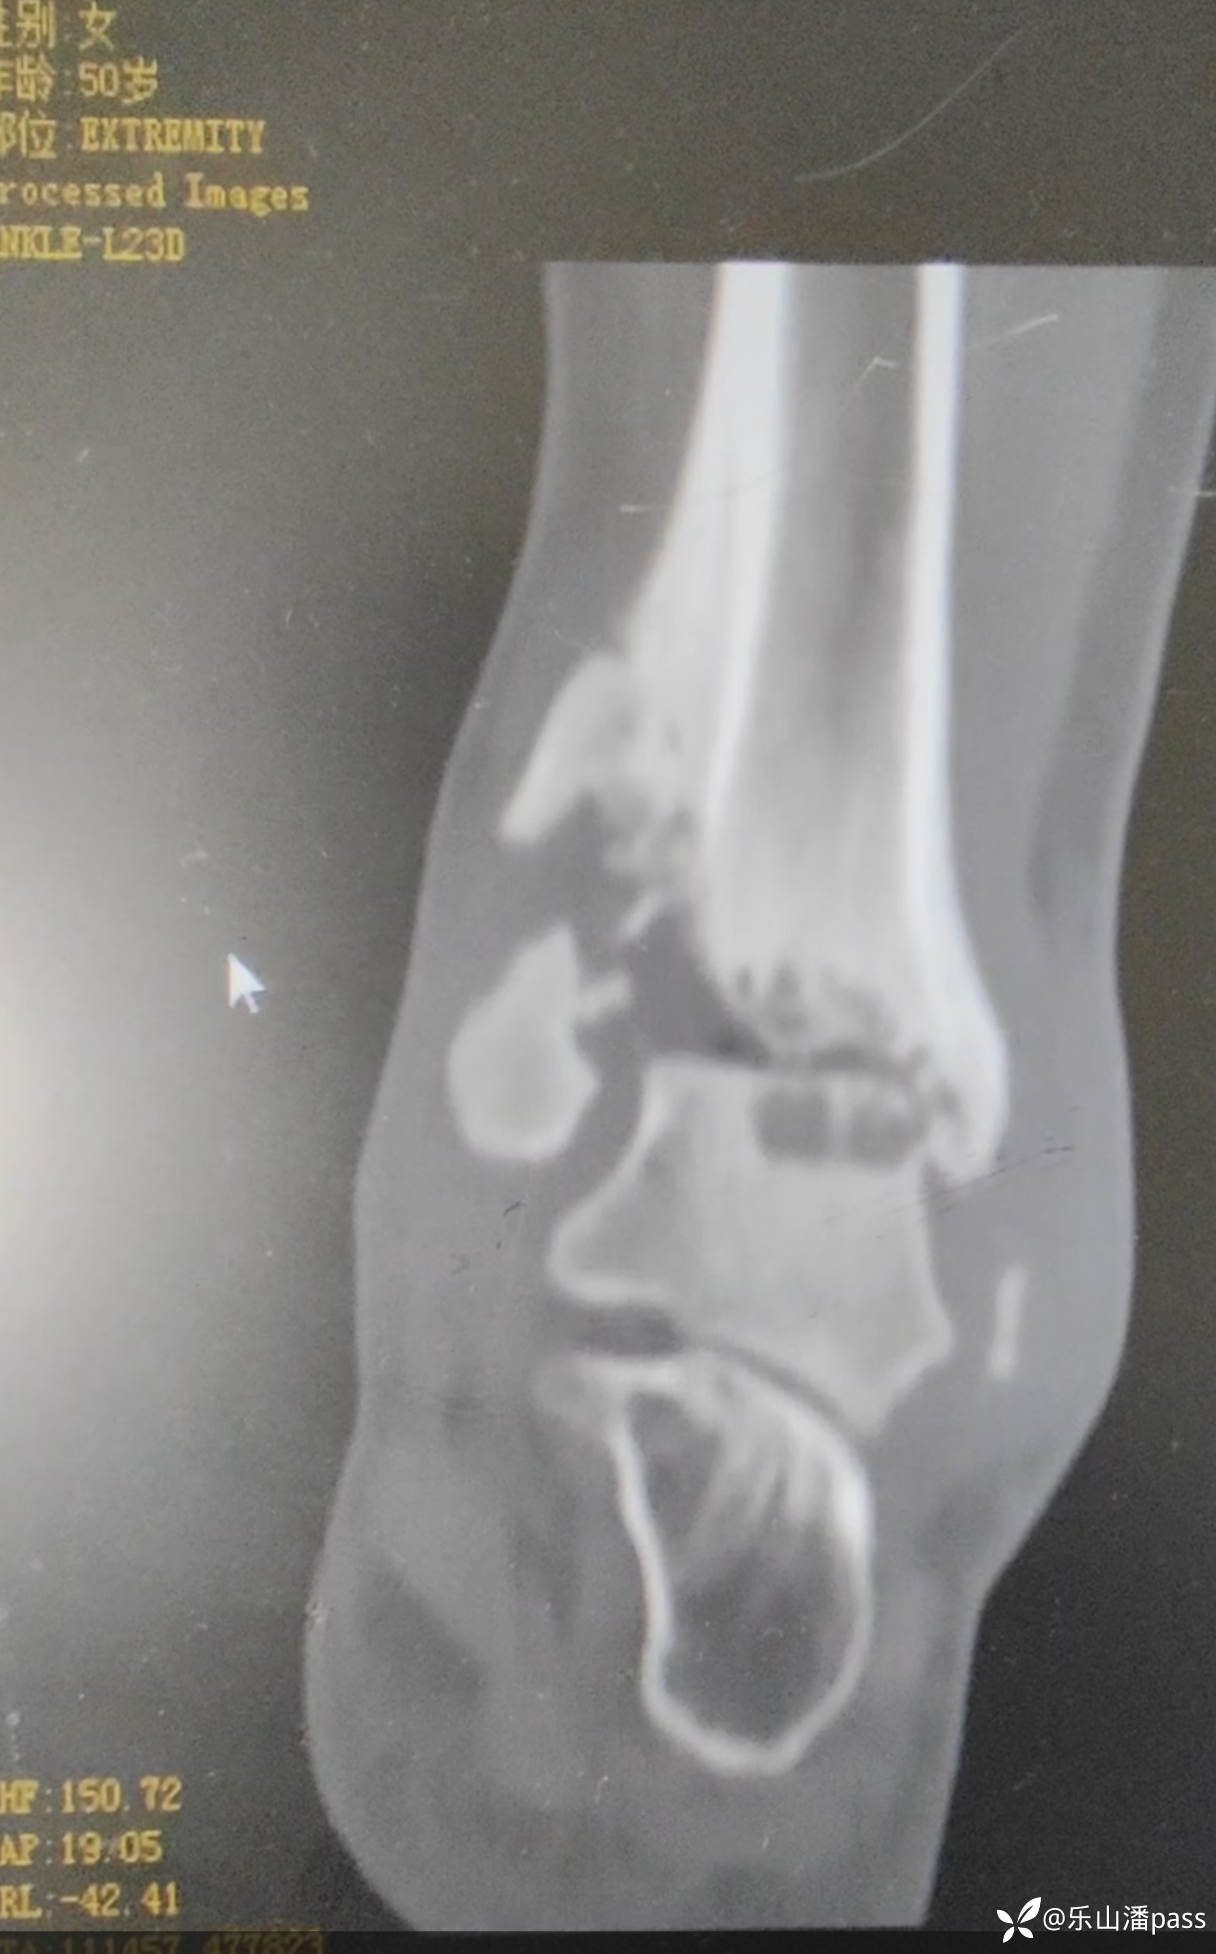

结果,现患者疼痛,来我院检查

img

瞬间傻眼了!

拟手术治疗,方案?

骨折 (1441)

骨缺损 (43)

踝关节半脱位 (5)